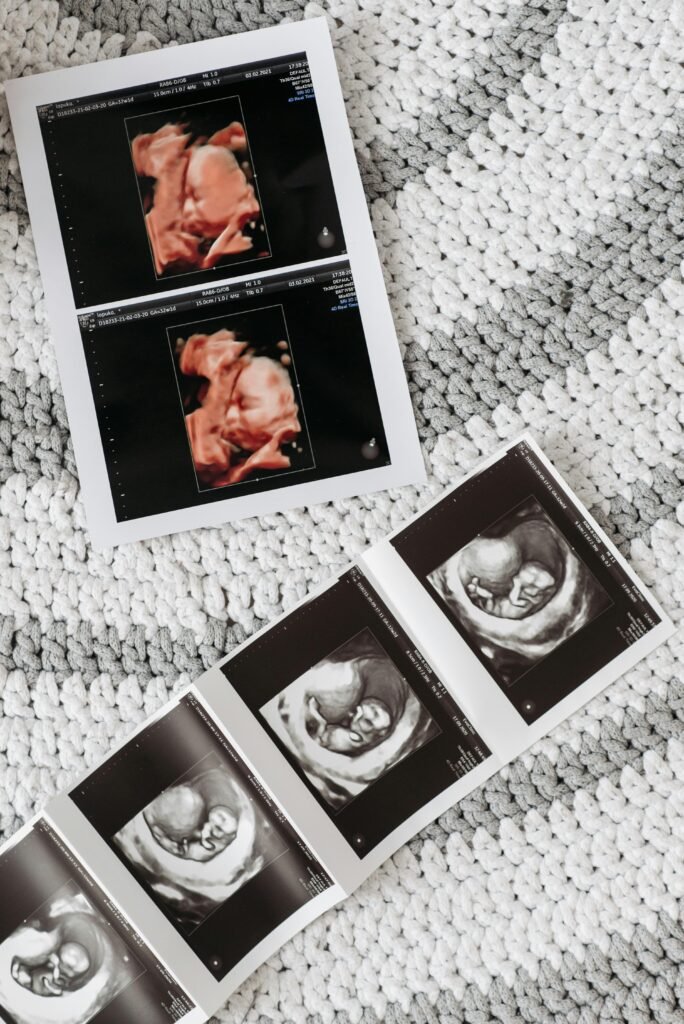

At American Fertility Centre — Sharjah, our IVF programme combines personalised medicine, skilled reproductive specialists and a modern micromanipulation laboratory to guide couples and individuals through every stage of assisted conception — from pre-IVF assessment to embryo transfer and follow-up care. IVF (in-vitro fertilisation) involves retrieving eggs, fertilising them with sperm in a laboratory, then transferring one or more healthy embryos to the uterus.